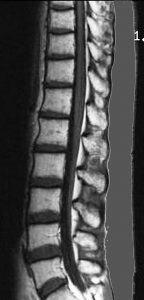

20歳くらいから尿崩症があり,2年後に汎下垂体機能低下症と軽度の認知機能低下を生じました。脳室壁と松果体,神経下垂体にジャーミノーマが広がっているのですが,脊髄背面と脳幹部の周囲にも腫瘍結節が見られました。脳室上衣以外の部位に腫瘍があるので,播種を疑いました。ジャーミノーマの播種というのは実際にはとても珍しくてなかなかみないものです。HCGは軽度の上昇,鼻孔から下垂体部分を生検して病理確定診断して,化学療法と脳脊髄照射 25.2Gy をしました。腫瘍は1コース目の化学療法でほとんど消失したので,他の組織型の悪性混合性胚細胞腫瘍ではないと考えられます。

3年後に脳室壁に再発しました。脳梁と脳弓の機能低下があり認知機能低下は高度でした。松果体と神経下垂体には再発はありません。

脊髄にも再発は見られませんでした。